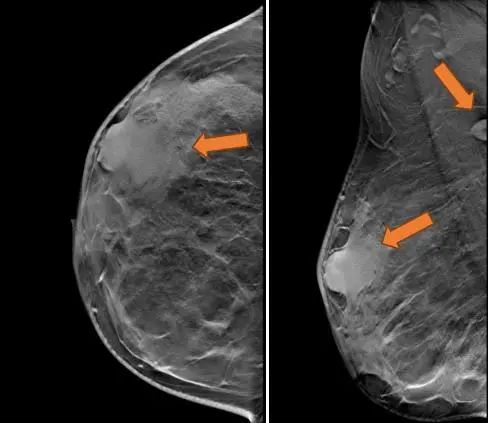

(3 cycle 后)2021.9.21 钼靶示:右乳外上象限不规则形肿块明显缩小,右腋窝淋巴结亦较前缩小。

图6. 钼靶

(3 cycle 后)2021.9.22 复查乳腺MRI示:右乳肿块较前减小14mm×9mm×18mm。

图7. 乳腺MRI

本例是一位年轻的乳腺癌患者,经穿刺右乳肿物确诊为HER2阳性型,虽然遗憾的是右腋窝淋巴结未行穿刺,但根据乳腺超声、钼靶及乳腺MRI,腋窝淋巴结转移的可能性较大,首诊右乳癌cT2N1M0 Ⅱb期,根据CSCO、NCCN等指南推荐,建议此患者进行新辅助化疗,推荐方案为TCbHP或THP,考虑患者较年轻,后续生存质量及可能会有生育要求,建议其化疗前使用OFS保护卵巢,患者拒绝。结合患者肿瘤类型及自身情况,为患者选择了双靶联合单药化疗THP方案,其中H为国产曲妥珠单抗汉曲优,经过两个周期的新辅助化疗后,患者自我感觉及乳腺超声均提示右乳肿物明显缩小,大大增强了患者战胜癌症的信心,第三周期化疗后全面复查,临床查体右乳外上象限肿物体表无法触及,影像学乳腺超声、钼靶及乳腺MRI评估提示右乳肿物明显缩小,右腋窝肿大淋巴结明显缩小,消失。由于患者出现了化疗后重度骨髓抑制,虽然经处理好转,但患者拒绝继续按原计划行新辅助化疗6周期,要求手术治疗。于2021.9.23全麻下行右乳癌改良根治术,可喜的是,病理结果提示右乳癌肿达到了完全病理缓解。